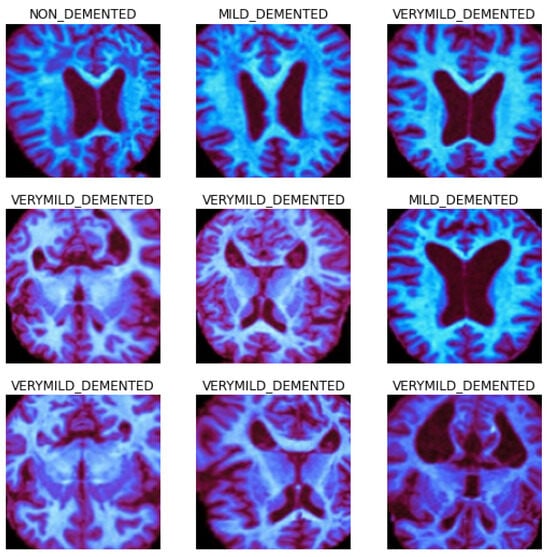

3. Description of Alzheimer’s MRI Datasets